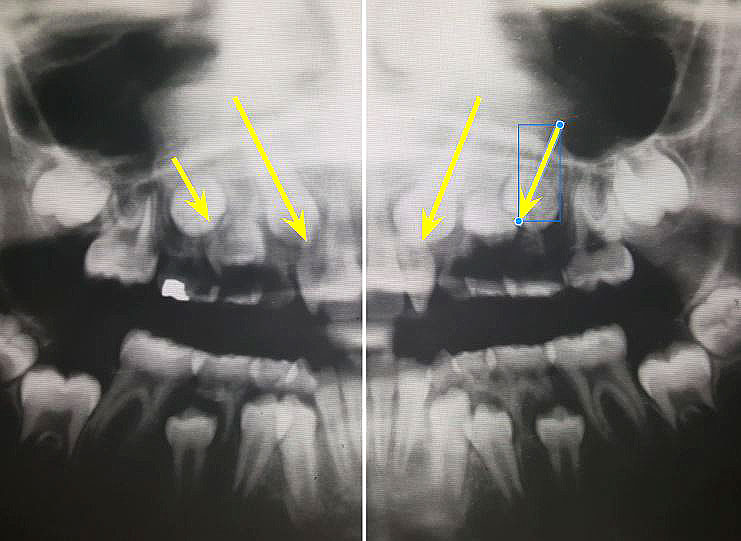

Photo 1 shows permanent lateral incisors with badly damaged roots due to the permanent canines coming in slanted instead of straight.

Photos 2

Photo 2 shows what is looks like when a canine comes into the wrong place